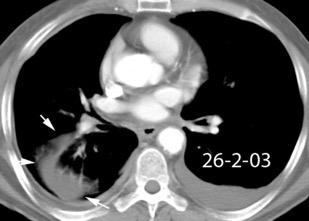

Paciente que ingresa con síntomas de colecistitis aguda. Antecedentes de trauma importante muchos años antes

Zhao L et al. Delayed traumatic diaphragmatic rupture: diagnosis and surgical treatment. © Journal of Thoracic Disease.

J Thorac Dis 2021

Asas

Líquido pericolecistítico

V. biliar con cálculos

Diafragma